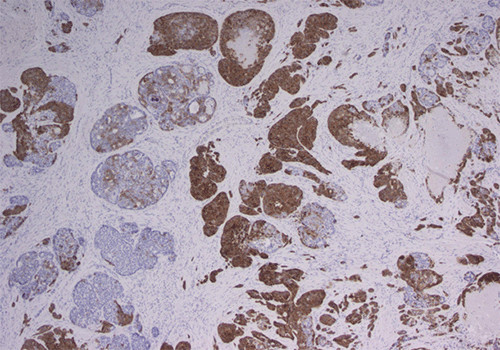

Final pathology revealed a 3.5 cm mixed neuroendocrine-non-neuroendocrine neoplasm (MiNEN) with perineural invasion (Figures 2A and 2B); resection margins were negative for malignancy. Ten lymph nodes were resected, and all were negative for malignancy.

Figure 2. Histopathologic Features of of MiNEN Tumor with Distinct Morphology. Published with Permission

(B) Ki-67 stain (40x magnification) showing a high proliferation index within the adenocarcinoma component and a significantly lower proliferation index in the neuroendocrine component

(D) Synaptophysin stain (40x magnification) demonstrating a dual population of tumor cells, highlighting the neuroendocrine component

The tumor consisted of 35% WHO grade 3, well-differentiated neuroendocrine tumor with a 30% proliferation index, and 65% poorly differentiated adenocarcinoma with an 80% proliferation index. The tumor was staged as pT3N0. Immunohistochemical staining showed the tumor to be positive for AE1/AE3 and variably immunoreactive for synaptophysin, chromogranin, and INSM1. Scattered tumor cells were positive for CK20, and the tumor was negative for CK7. Following discussion at the multidisciplinary tumor board, adjuvant FOLFOX chemotherapy was recommended. To date, surveillance imaging has shown no evidence of recurrence or metastatic disease within the abdomen.